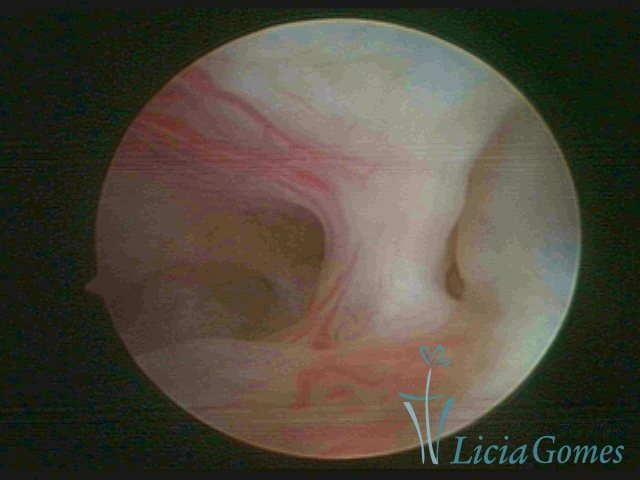

FIBROUS SYNECHIA

Uterine synechiae are scars (adherence) between the surface of the uterine walls, which may occur after the surgical procedure, uterine curettage, or after an inflammatory process in the uterine cavity (endometritis), which may lead to menstrual changes, infertility and obstetric complication such as abortion and premature birth.

• SINÉQUIA TIPO FIBROMUSCULAR